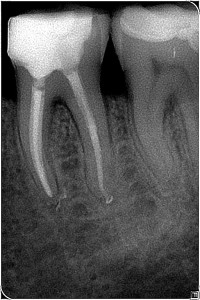

Fallbeispiel-2_Bild_5_Pat_781_Za_36_R__ntgenkontrolle_n_4_Monaten Posted on 5. Februar 201615. Februar 2016 by Administrator